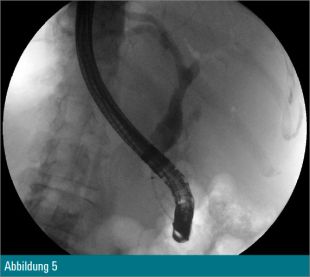

Eine 55-jährige Patientin wurde wegen eines Tonnenkonkrements im Ductus choledochus zur ERCP vorstellig (Abbildung 1). Nach Papillotomie erfolgte zusätzlich eine Ballondilatation der Papille auf 12 mm. Anschließend wurde mit dem Cholangioskop in den Ductus choledochus eingegangen (Abbildung 2) und eine elektrohydraulische Zertrümmerung des Konkrements unternommen (Abbildung 3).

Trotz Fragmentierung des Konkrements (Abbildung 4) waren mehrfache mechanische Lithotripsien mit dem Dormiakörbchen in derselben Sitzung notwendig. Schlussendlich konnten alle Fragmente erfolgreich mit dem Ballon geborgen werden (Abbildung 5).